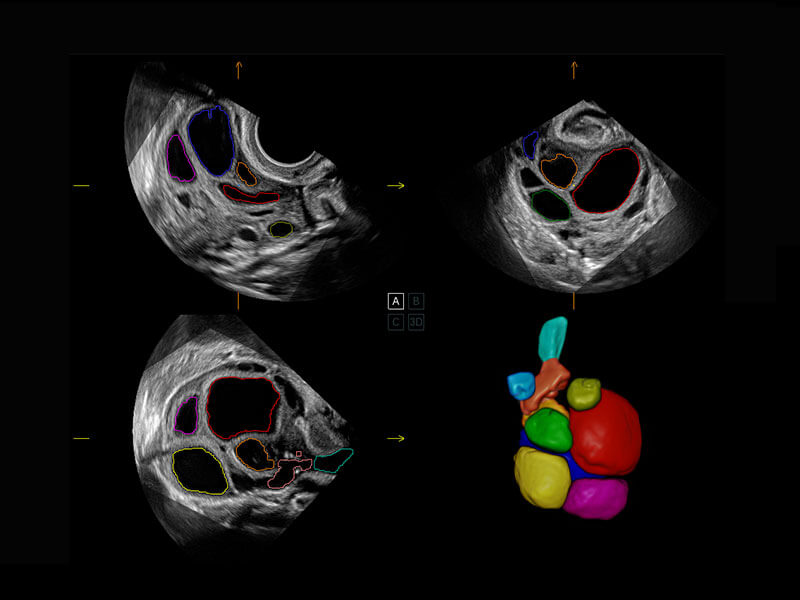

中晚孕筛查

P60提供简单易学易用的高端诊断工具,为您中晚孕筛查提供快速清晰的解剖信息。

1 OFD(HC): 87.03 mm

HC: 251.00 mm

GA: 27w 1d

HC/AC: 96.13 %

2 BPD: 70.56 mm

GA: 28 w 2d

S-Fetus(acq.)

& S-Fetus(meas.)

S-Fetus

S-Fetus能够助您在实时扫查过程中自动识别标准切面、自动测量并录入报告。一个按键,即可快速、高效地获取胎儿生理指标,简化您的产科检查操作。